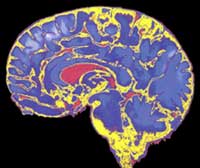

Imagen NMR (Nuclear Magnetic Resonance) de un cráneo humano

Sección del cerebro humano

También supone un gran reto entender el funcionamiento de procesos de un alto grado de complejidad y poder asociarlo con el funcionamiento de cada una de sus partes. En el caso del funcionamiento del cerebro, por ejemplo, ¡sería estupendo entender las bases morfológicas y fisiológicas del funcionamiento del cerebro!